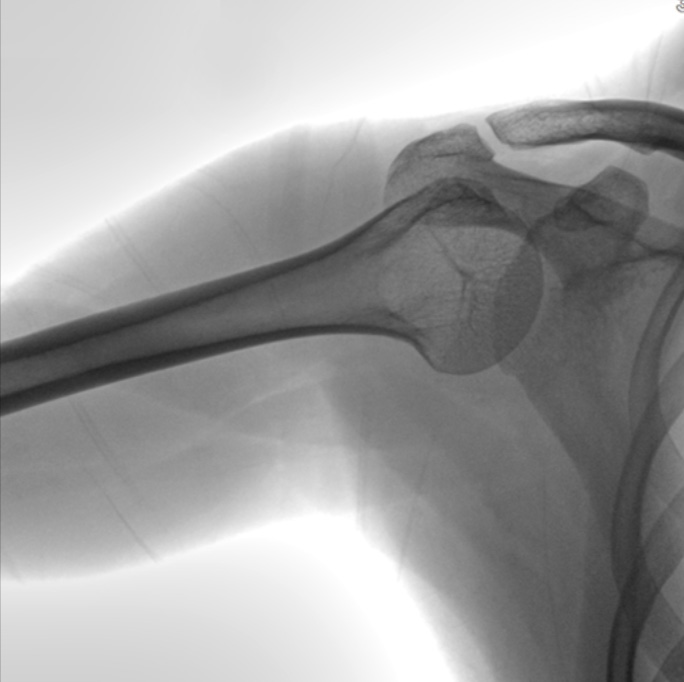

3) Spatial Resolution(lp/mm): 3.3

4) Pixel Matrix( pixels): 1024×1024

5) Pixel Pitch(um): 105

7) Active area(mm): 307.2 x307.2